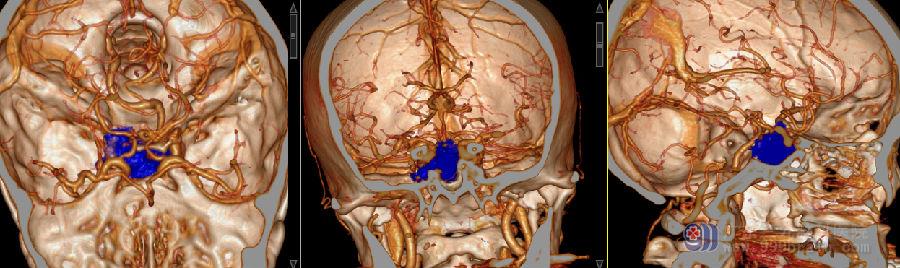

图:1:术前头颅CTA检查示鞍区示一团块状等、低密度影,向下突入蝶窦,病变血供丰富,包绕右侧颈内动脉,左侧颈内动脉受压外移;右侧海绵窦受侵。左椎动脉起源于主动脉弓左颈总动脉后方。右侧椎动脉及颈总动脉开口位置正常。左侧椎动脉较对侧稍细小,未见明显粗细不均。双侧大脑前、中与后动脉、双侧颈总与颈内动脉、右侧椎动脉及基底动脉走行稍僵直,双侧颈内动脉虹吸部示钙化斑。双侧颈内动脉起始部示弧形低密度影。双侧大脑后动脉由后交通动脉供血。甲状腺双侧叶示多发小结节状低密度影。